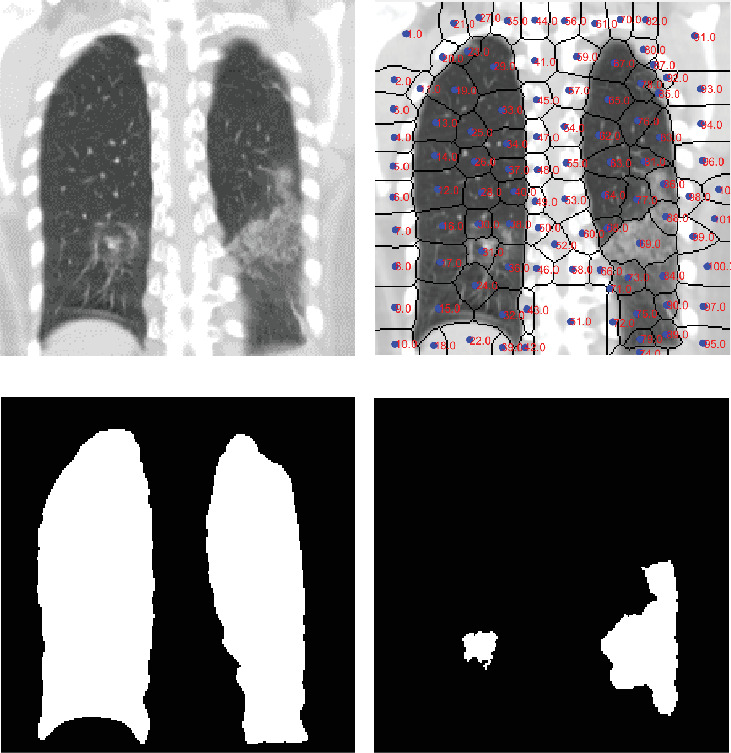

This study proposes an automated system for assessing lung damage severity in coronavirus disease 2019 (COVID-19) patients using computed tomography (CT) images. These preprocessed CT images identify the extent of pulmonary parenchyma (PP) and ground-glass opacity and pulmonary infiltrates (GGO-PIs). Two types of images-saliency (Q) image and discrete cosine transform (DCT) energy image-were generated from these images. A final fused (FF) image combining Q and DCT of PP and GGO-PI images was then obtained. Five convolutional neural networks (CNNs) and five classic classification techniques, trained using FF and grayscale PP images, were tested. Our study is aimed at showing that a CNN model, with preprocessed images as input, has significant advantages over grayscale images. Previous work in this field primarily focused on grayscale images, which presented some limitations. This paper demonstrates how optimal results can be obtained by using the FF image rather than just the grayscale PP image. As a result, CNN models outperformed traditional artificial intelligence classification techniques. Of these, Vgg16Net performed best, delivering top-tier classification results for COVID-19 severity assessment, with a recall rate of 95.38%, precision of 96%, accuracy of 95.84%, and area under the receiver operating characteristic (AUROC) curve of 0.9585; in addition, the Vgg16Net delivers the lowest false negative (FN) results. The dataset, comprising 44 COVID-19 patients, was split equally, with half used for training and half for testing.

Abstract Image